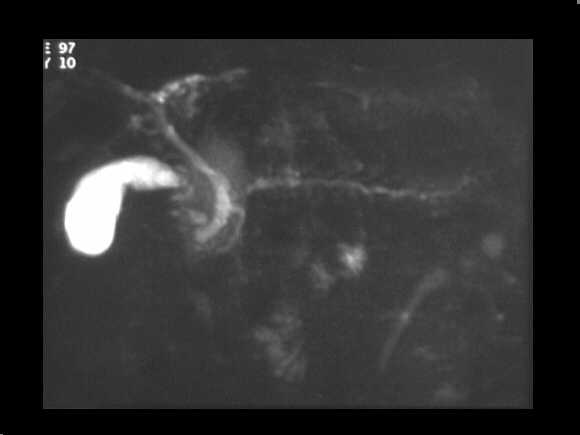

Obstructive chronic pancreatitis. MRCP examination demonstrates the chain of lakes pattern of the MPD. The CBD is also dilated.

MRCP examination demonstrates the chain of lakes pattern of the MPD. The CBD is

also dilated.